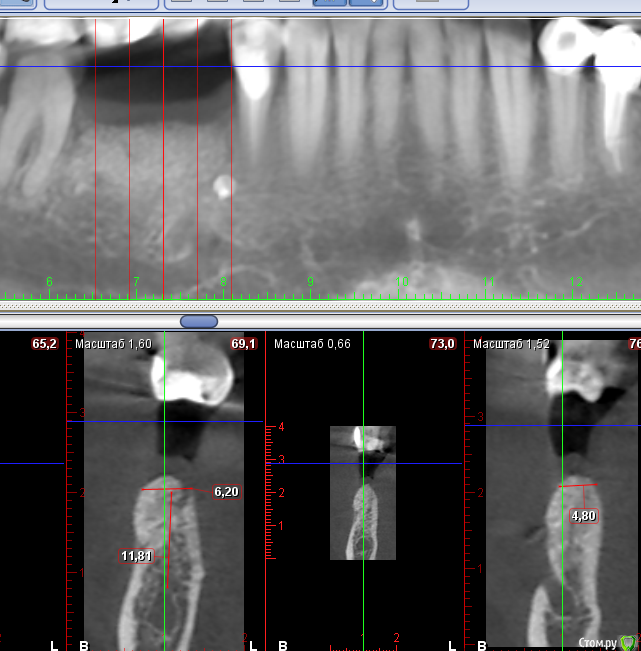

Sergiosse Опубликовано 16 мая, 2018 Поделиться Опубликовано 16 мая, 2018 (изменено) Делал нкр 5 месяцев назад ауто + церабон1:1 под резорбируемую мембрану. ширины для установки импланта всё равно недостаточно. Размышляю над расщеплением или использованием конденсаторов. У кого был подобный опыт сновообразованой образованный костью. Опасаюсь обколоть массив графта. И ещё вопрос между графом и гребнем на левом скриншоте есть темная полоска, это вросла десна? Изменено 16 мая, 2018 пользователем Sergiosse Ссылка на комментарий

Тимур86 Опубликовано 16 мая, 2018 Поделиться Опубликовано 16 мая, 2018 Можно заглубиться ещё на 1мм и не понадобится ничего.Да,скорее всего это десна... Ссылка на комментарий

Nazim_NV86 Опубликовано 19 мая, 2018 Поделиться Опубликовано 19 мая, 2018 (изменено) Экспандерами вы можете разломать свой графт. Если диском пройдетесь и стамеской за ней то +1-1,5мм можно получить. Изменено 19 мая, 2018 пользователем Nazim_NV86 Ссылка на комментарий

voff Опубликовано 21 мая, 2018 Поделиться Опубликовано 21 мая, 2018 (изменено) По моему опыту, расщепление не пойдет, тонкие и короткие импланты.47 удалить, по всем фронтам хана ему Изменено 21 мая, 2018 пользователем voff Ссылка на комментарий